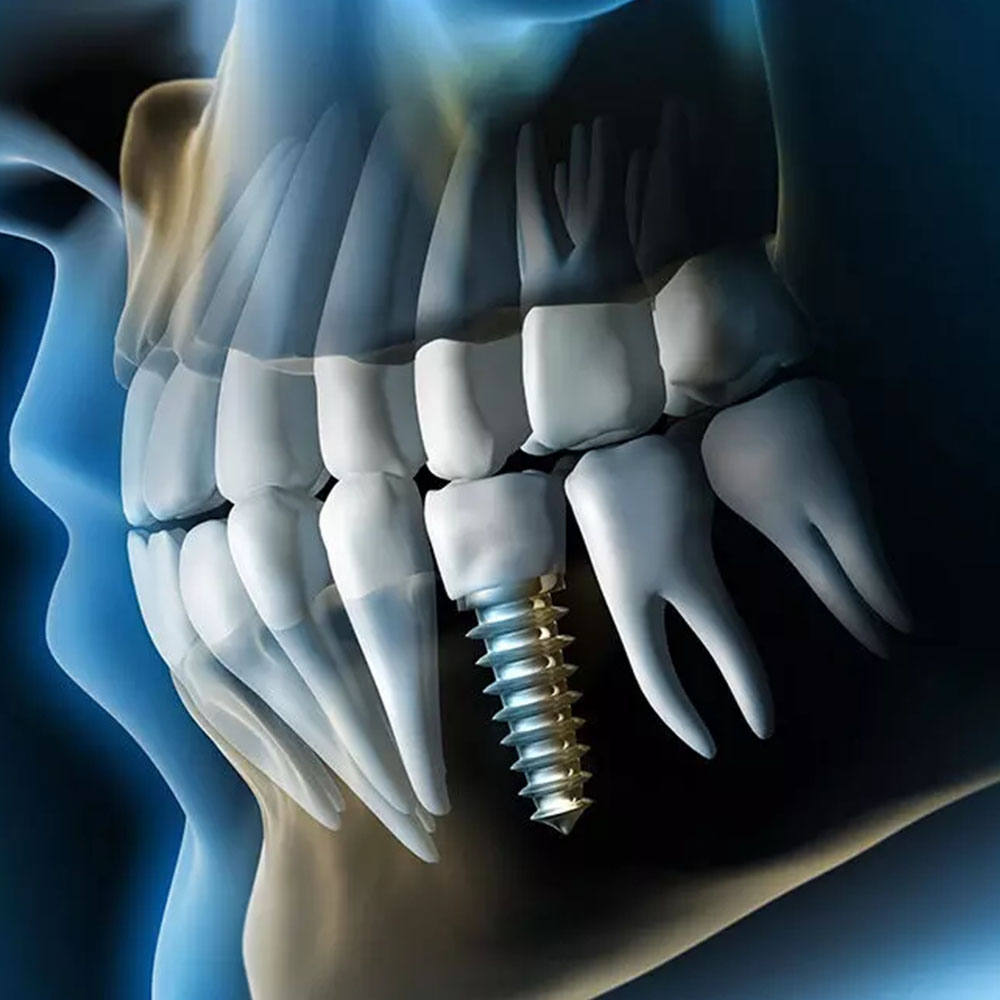

Implanturile dentare sunt concepute să funcționeze ca rădăcini artificiale, oferind un suport solid pentru coroanele, puntile sau protezele dentare, indiferent dacă lipsește un singur dinte sau mai mulți

Evaluarea personalizată pe care o oferim fiecărui pacient reprezintă un prim pas esențial în procesul de implantologie. În timpul acestei etape, echipa noastră de specialiști în implantologie analizează atent starea actuală a sănătății orale a pacientului. Acest proces implică examinarea atentă a structurii osoase a maxilarului sau mandibulei, determinând dacă există suficient os disponibil pentru plasarea implantului dentar.

Plasarea implantului dentar reprezintă un proces meticulos și precis, în care punem accent pe fiecare detaliu pentru a asigura succesul intervenției. Utilizăm tehnologii de ultimă generație și materiale de cea mai înaltă calitate pentru a obține rezultate excepționale.

În timpul procedurii de plasare a implantului, echipa noastră de specialiști în implantologie lucrează cu mare atenție pentru a crea un mediu optim pentru integrarea implantului în osul maxilar sau mandibular.